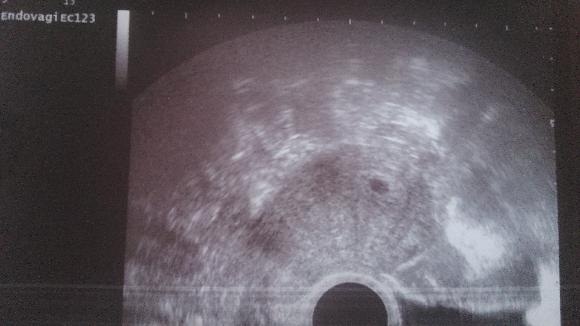

@bubulina1983 😀 Představ si, ten den 25.3. co jsem nastoupila k té nové doktorce, jak jsem psala, že mi doporučila ten inofolic atd..tak na ult byla velká sliznice a cysta po OVU 😀 a říká mi noo tak to máme krásně připravený na ms 😀 ha jenže ono už to bylo těhu 😀 No a inofolic že si koupím, jak dojde MS, ať začnu pěkně od znova....ještě jsem měla s ms jít na krev na HP. Noo a ms furt nikde, už furt křeče, lítala jsem na wc, že to dojde. Prsa mě nebolely, prostě nic. Jen divný kříčky v bříšku. No když už to bylo 28dní 29 dní, tak jsem řekla no nic, zkusím test. tak myslím 30 DC (mívám právě kolem 26-27) jsem udělala test a byl tam dušík, pak ob dva dny a sílil. To bylo 2.4. čtvrtek. No a v pondělí jsem zavolala sestře. že čekám na ms a furt nic a že mám //, tak mě objednala na ult 10.4. a byla tam bublinka = fazolka. No nevěřila jsem, ani manžel ne. Prostě po těch letech vůbec. Manžel prej ty jo, tomu nevěřím a testu už vůbec ne 😀 a jak jsem donesla domů fotku, tak už uvěřil. Ale víme, že vyhráno není, teprve teď fakt začíná stres, aby bylo vše ok. No a jak se to povedlo? 😀 Já vůbec nevím 😀 Třetí cyklus jsem měřila BT (rozhodla se to zkusit, jestli tu ovlku mám) no a jak se to blížilo že by mohla být, i hleník..tak jsme to večer pojistili, prostě rychlovka 😀 . Takže tak nějak samo prostě. Já si mezitím na květen domluvila spoustu akcí, sraz na víkend se psy atd. takže to pak musím zase rušit..fakt jsem s tím nepočítala, žila jsem s tím, že to nevadí, že na IVF bychom šli kdyžtak do toho Brna a teď si užijeme léto ... jo a v únoru jsme si koupili chatičku se zahradou, takže o víkendech dam pleju, uklízíme..pohodička..možná to. tam prostě fakt vypnu a jsem bez starostí.

@luca16 nezapomenu na vás holky moje...však jsem tu skupinku tady založila a to by nešlo, vás tady opustit 😀 . Budu poctivě hlásit. a tak hned dávám první fotečku co mám a dnes jdu v poledne jestli už máme srdíčko, tak snad dostanu druhou 🙂.